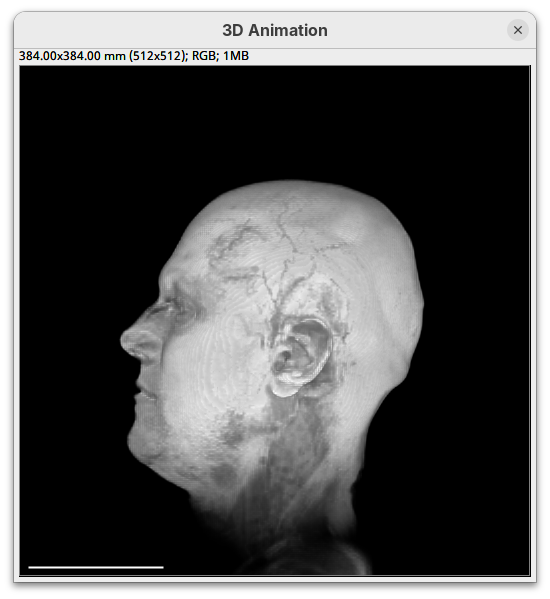

Plugins>3Dscript>Interactive Animation.

Two new windows will open: 3D Animation with the initial rendering of the data and Interactive Raycaster with all the fields to control the rendering parameters.

Contrast

The Contrast section shows a histogram of pixel intensities of the image for each channel, which we can choose using the dropdown menu. We can set the minimum, gamma, and maximum values for the intensity and alpha (transparency) properties of each pixel. The weight option controls the general opacity of the channel (0=invisible, 100=visible). There’s also more advanced options like lighting and rendering algorithm which we’ll simply use the default states as they are usually good for most use cases.

Adjusting the intensity and alpha values is the most impactful way to improve the 3D rendering. With the intensity setting we can define which pixel value in the image corresponds to total black (minimum) and which corresponds to total white. It’s the same as in the standard Brightness & Contrast tool. By default, 3Dscript will load these values from the original stack. In this case, it loaded min=3 and max=521.

Let’s change these values to see how it impacts the 3D rendering.

- Change the intensity minimum to

250.

You will see that the darkest parts of the rendering will become even darker and no longer visible. We are losing real information from the data; we do not want that.

- Set the

minto0, for now. - Then, change the

maxto250.

The brightest parts of the rendering will become all white. It is so bright that we can no longer resolve details of the surface. We are losing information and also do not want that.

maxto500.

Note that when you change an intensity value, the min/max black line in the histogram moves. You can also grab the line and move it manually to change the values.

The blue line represents the alpha values. In 3D rendering, a pixel has a transparency value linked to its intensity. The alpha min defines the value for full transparency and the max the value for full opacity.

- Set the alpha

minto250.

This will make darker pixels more transparent and information gets lost.

- Set it to

0.

By default 3Dscript sets the gamma value of alpha to 2.0. That’s a good default for fluorescence microscopy (see the next dataset below), but since this is MRI data, we need to tweak it a little differently.

- Set the alpha gamma value to

1.0.

Note that this improves the visualization as the head’s surface becomes better visible.

- Now set the alpha

The surface will become even more solid because we are defining that pixels that have a value above 250 will be fully opaque.

- To compare, set alpha

maxto5000.

You will notice that the sample will become more transparent. Even the brain inside the skull will be visible.

- Set alpha

maxback to500.

Generally, setting the intensity and alpha to the same values is a good starting point for optimizing the rendering.